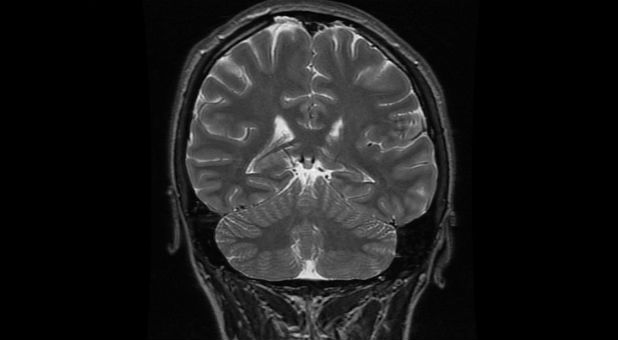

In a study conducted by University of Pennsylvania researchers, scientists tracked the blood flow through the brain as women spoke in tongues and sang gospel songs.

By comparing the patterns created by these two emotional, devotional activities, the researchers could pinpoint blood-flow peaks and valleys unique to speaking in tongues, The New York Times reports.